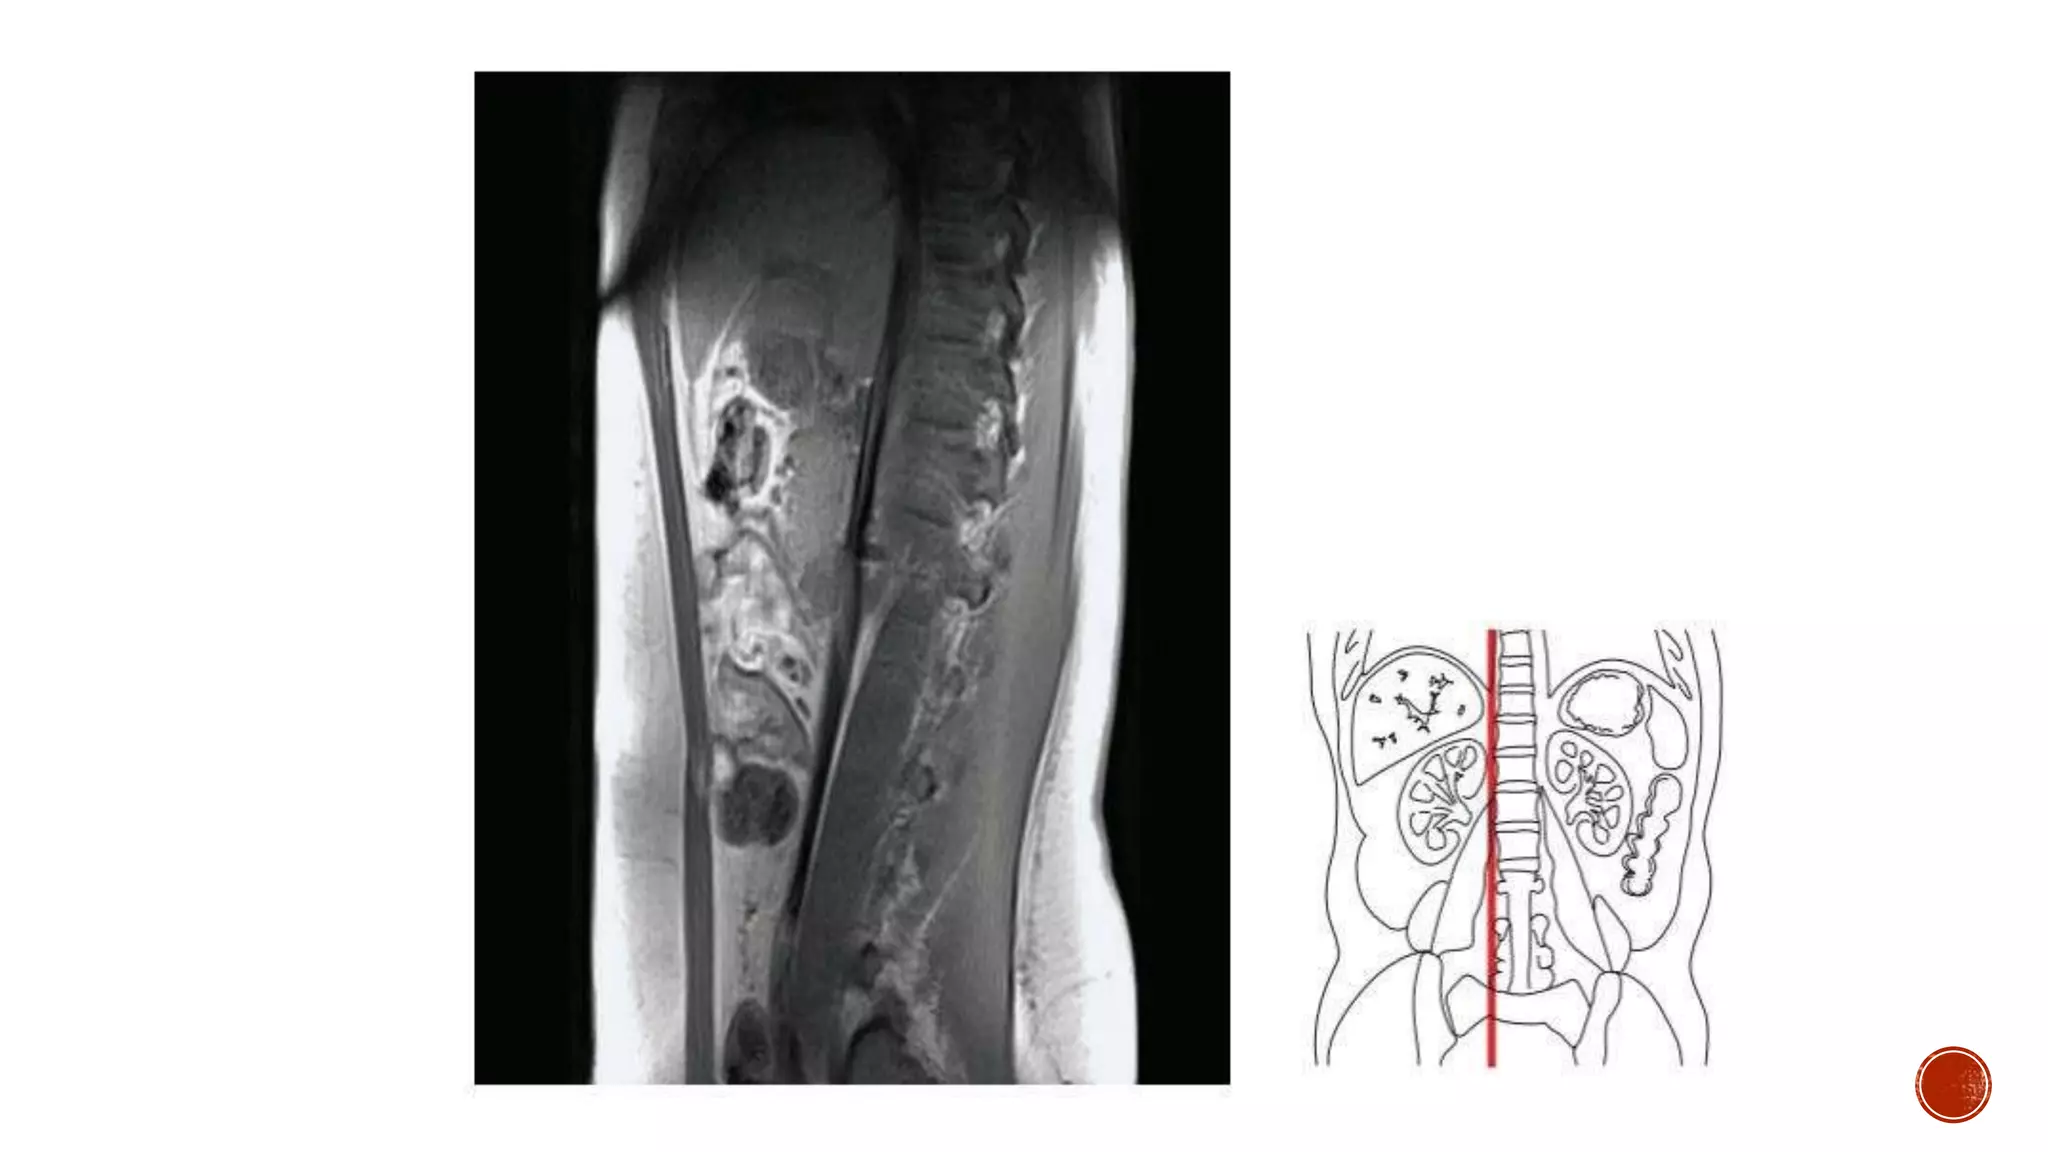

The document describes the anatomy of the abdomen and pelvis region of the human body. It lists over 40 structures and their locations, including major organs like the liver, kidneys, intestines, blood vessels and muscles of the abdominal wall and pelvis. The structures are grouped into sections focusing on different anatomical areas like the abdomen, retroperitoneum, pelvis and gluteal region.